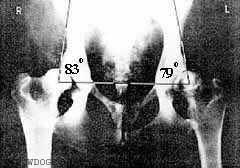

Дисплазия 3 степени:

угол Норберга 90 градусов;

- сильно уплощенная вертлужная

впадина;

- явления остеоартрита;

- суставные поверхности не

конгруэнтны;

- деформация головки бедра и ее

подвывих.

Дисплазия 4 степени:

- те же изменения, что и при

дисплазии 3 степени;

- полный вывих головки бедренной

кости.